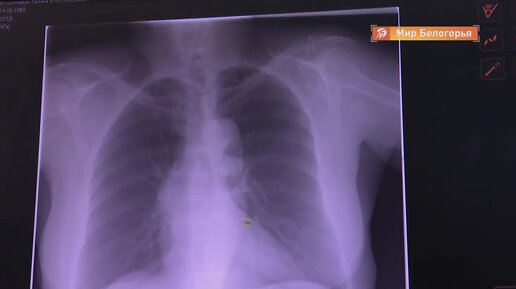

Сенсационное открытие ученых! Теперь определить ковид можно за несколько секунд